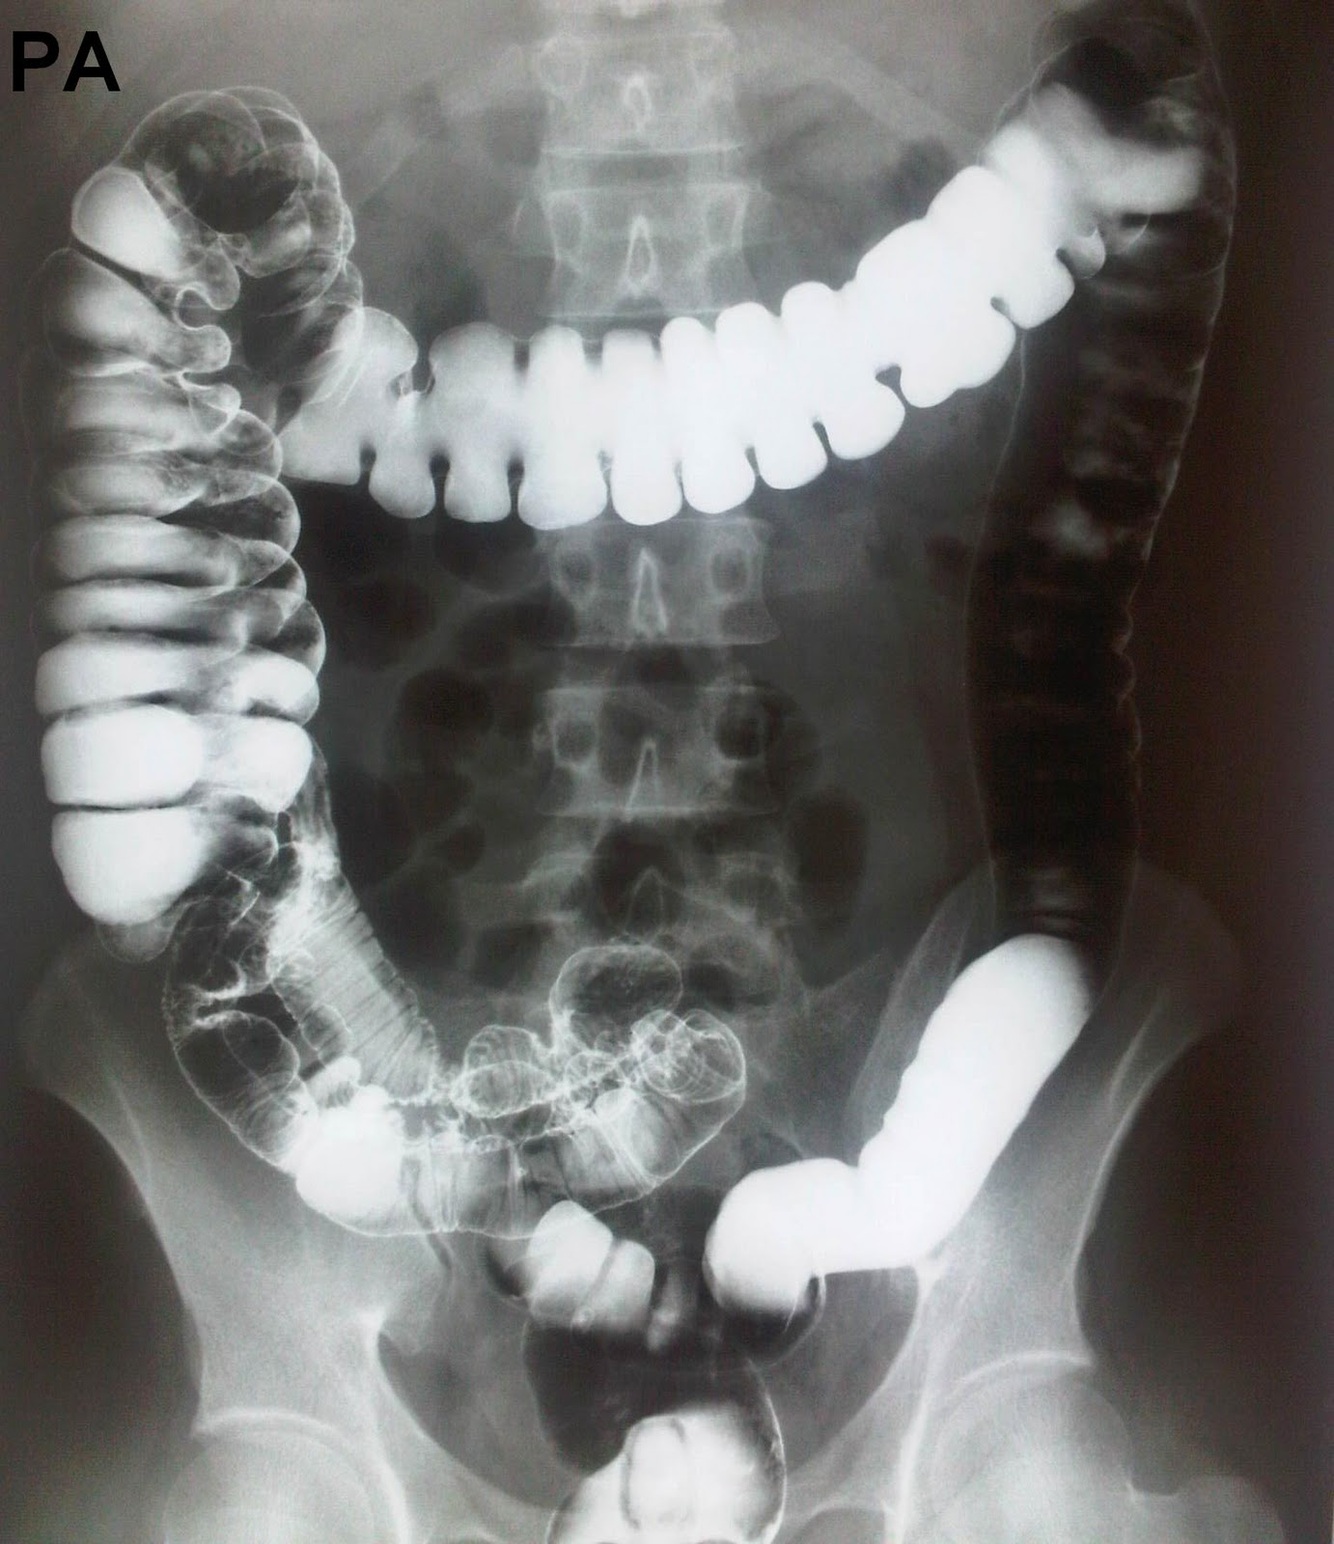

Rx Colon por Enema

Se utiliza doble contraste (bario + aire):

* Útil para investigar neoplasias, estenosis inflamatorias, divertículos y determinar el tamaño colónico.

* Se debe realizar en todos los pacientes constipados, salvo en los casos que el estreñimiento es pasajero.

* Enfermedad de Hirschsprung: La porción enferma (aganglionar) aparece como un segmento estrecho y por encima un colon muy dilatado o megacolon.